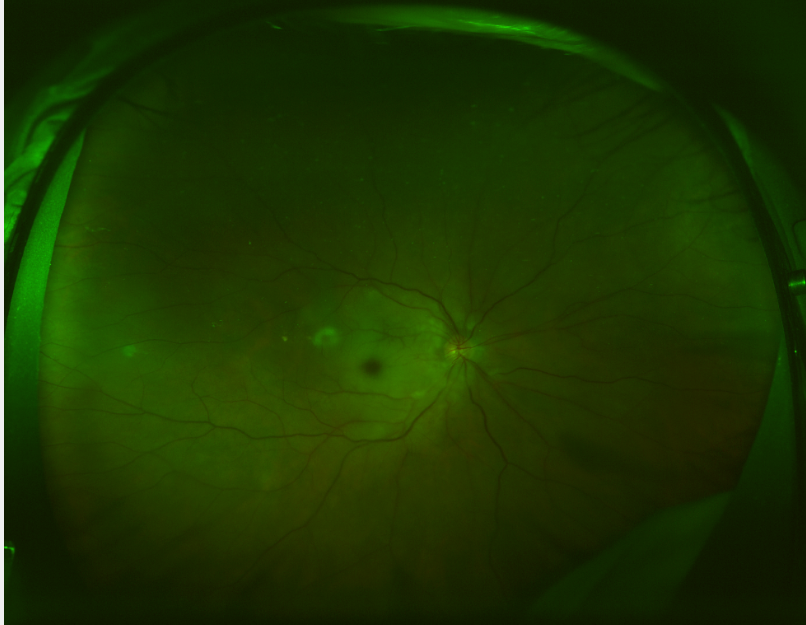

▲高阿伯右眼欧堡超广角眼底照片

经检查,阿伯右眼视网膜已经灰白、水肿,黄斑中心呈樱桃红改变,动脉变细,确诊为右眼视网膜中央动脉堵塞。因为阿伯已经错过最佳治疗时机,经过治疗,阿伯右眼的视力虽然有了明显提高,但只能恢复到FC/10cm(能辨认眼前10cm处手指指数)。